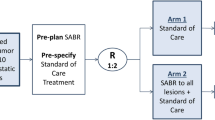

Until fairly recently, RT of metastases was considered to be palliative only. The above recent advances in imaging and biological targeting, however, provide support for SBRT with curative intent in an oligometastatic setting although, as yet, there is no consensus on schedule (optimal doses, number of fractions, and treatment delivery accuracy). The efficacy of SBRT is well established for liver oligometastases but less well established, although promising, for abdominal LN metastases (one 5-year study) and adrenal gland oligometastases (survival similar to surgical resection for solitary adrenal metastases). Further prospective studies are needed to confirm these results.

Distant metastases are the main cause of death after SBRT. Chemoradiotherapy thus deserves study. Chemotherapy increases organ sensitivity to radiation and also kills tumour cells disseminated in the blood. Promising antitumour responses without potentiation of RT toxicity were observed in a Phase I study of concurrent sunitinib and hypofractionated IGRT followed by maintenance sunitinib in patients with oligometastases [67]. A multi-institutional Phase II trial is ongoing. In 2007, we initiated a Phase II prospective multicentre study of SBRT and concurrent irinotecan in colorectal cancer patients with unresectable liver and lung metastases. As preliminary results for the combination did not differ significantly from those for SBRT alone, we increased the tumoricidal dose in order to achieve higher LC [68]. The study is ongoing.

In conclusion, published studies suggest that SBRT is a valuable alternative to surgery in patients with liver or abdominal lymph node oligometastases although no SBRT standards have yet been defined for the latter. The value of SBRT in the treatment of adrenal oligometastases will depend on their early detection. Future attempts to improve outcomes could focus on including a SBRT plus chemotherapy arm in SBRT trials and identifying patients with oligometastatic disease by microRNA expression.